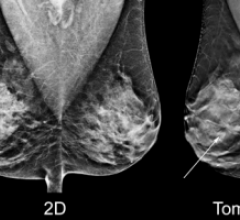

Hologic is a leading developer, manufacturer and supplier of premium diagnostic and medical imaging systems dedicated to serving the healthcare needs of women, and a leading developer of state-of-the-art digital imaging technology for general radiography and mammography applications. Our core business units are focused on osteoporosis assessment, mammography and breast biopsy, direct-to-digital x-ray for general radiography applications and mini C-arm imaging for orthopedic applications. Hologic has achieved a leading market position in breast cancer and osteoporosis detection in the United States. Our market share in the European, Asian and South American markets continues to grow. There is nothing more important than for us to remain dedicated to the principle of applying highly sophisticated technology to medical imaging challenges, and we are committed to being an active voice and a corporate role model in promoting women's health initiatives.